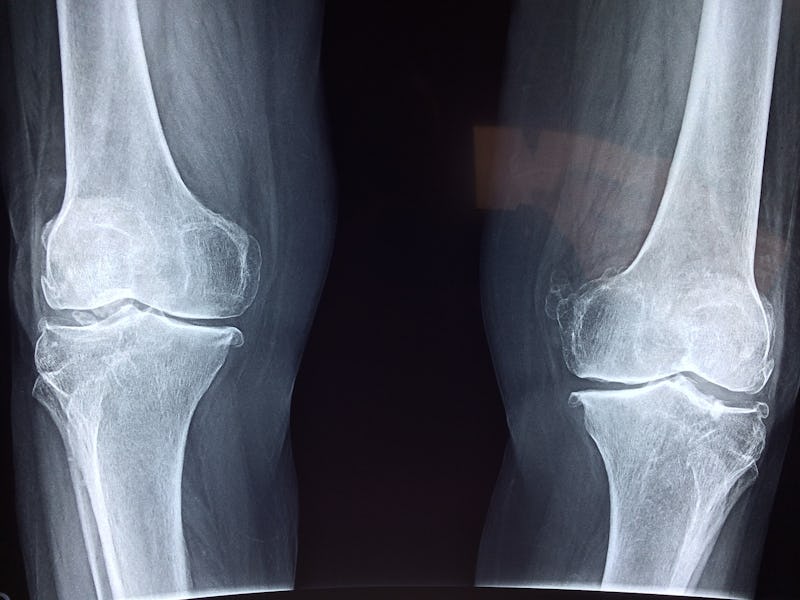

In orthopedics, researchers have proposed using stem cells for the treatment of joint cartilage damage. This includes osteoarthritis, the thinning of cartilage that causes bones to rub against one another — similar to a car tire going bald after 50,000 miles. Osteoarthritis is the primary cause of joint replacement surgery, and stem cell injections have been promoted as a potential way to avoid joint replacement by regenerating cartilage. Unfortunately, current technology and regulatory issues make obtaining and concentrating true stem cells a challenge, and encouraging them to become and remain cartilage cells and nothing else is even more difficult.

The problem with stem cells is that these cells can continue to evolve; they may not stop development at the cartilage cell phase. They may continue to differentiate into bone cells. This would make the joint even worse because bone creates a rough surface adjacent to the smooth articular cartilage. Bone is actually the end result of arthritis.